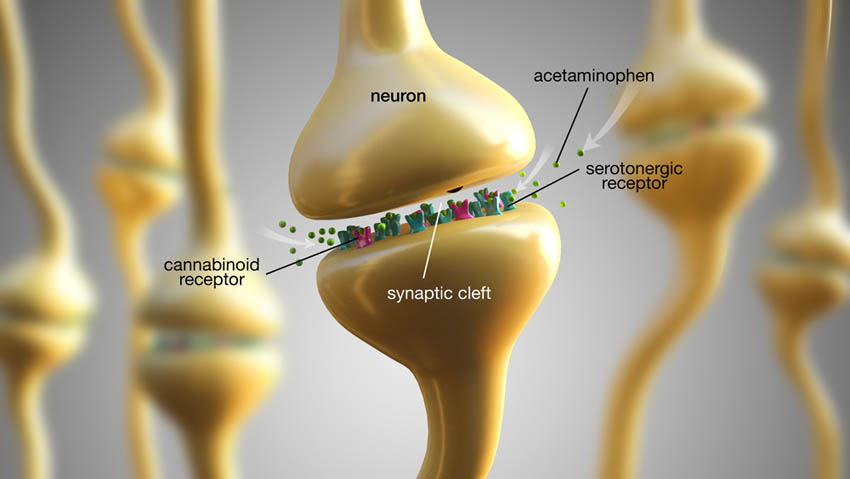

Παρόλο που η οριστική θεραπεία των οδοντικών καταστάσεων θα πρέπει να αποτελεί τον κύριο στόχο της παροχής περίθαλψης σε ασθενείς που πονούν και η τοπική αναισθησία μπορεί να βοηθήσει σε αυτό, μπορεί να είναι πλεονεκτική ή απαραίτητη η διαχείριση του πόνου με φάρμακα. Τα μη συνταγογραφούμενα φάρμακα που είναι χρήσιμα για την αντιμετώπιση του πόνου περιλαμβάνουν τόσο τα μη στεροειδή αντιφλεγμονώδη φάρμακα (ΜΣΑΦ) όσο και την ακεταμινοφαίνη (παρακεταμόλη). Η ιβουπροφαίνη είναι το πλέον μελετημένο ΜΣΑΦ για τον οδοντικό πόνο, πιθανώς λόγω του υψηλής ασφάλειας προφίλ του φαρμάκου αυτού και έχει βολική δοσολογία. Η ιβουπροφαίνη θεραπεύει τη φλεγμονή και εξασφαλίζει τη δράση της αποκλείοντας τα ένζυμα κυκλοοξυγενάση 1 και κυκλοοξυγενάση 2, τα οποία εμποδίζουν την παραγωγή προσταγλανδινών, οι οποίες εμπλέκονται στη μετάδοση του πόνου (Εικ. 3). Σύμφωνα με τον κατασκευαστή, η μέγιστη συνιστώμενη δόση ιβουπροφαίνης είναι 3.200 mg/ημέρα. Η ακεταμινοφαίνη έχει διπλή δράση: αναστέλλει τη σύνθεση της προσταγλανδίνης περιφερικά και δρα κεντρικά αλληλεπιδρώντας με τους κανναβινοειδείς και σερετονεργικούς υποδοχείς (Εικ. 4). Σύμφωνα με τον κατασκευαστή, η μέγιστη συνιστώμενη δόση ακεταμινοφαίνης είναι 3.000 mg/ημέρα.

κανναβινοειδής υποδοχέας

νευρώνας

συναπτική σχισμή

ακεταμινοφαίνη

σεροτονεργικός υποδοχέας